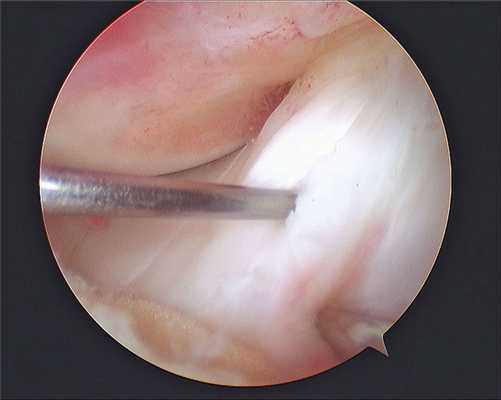

Изображение полости сустава.

В целях высокоинформативной диагностики специалист через микропортал вводит рабочую трубку устройства внутрь сустава, в которую вмонтированы система ультрасильных линз, мощный световой источник и видеозаписывающая цифровая техника. Все структуры, что «видит» артроскоп, визуализируются на экране в «живом» виде, причем изображение поступает в многократно увеличенном формате. Врач может найти точное расположение травмы или дегенеративных изменений, установить характер патологии, степень тяжести и принять меры.

Доказано, что артроскопия превосходит любые существующие способы диагностики. Она четко показывает изнутри все структурные единицы костного соединения в самых мельчайших подробностях, позволяет определить даже мелкие скрытые повреждения, которые нельзя выявить при помощи стандартной рентгеноскопии или артрографии, ультразвука, МРТ, КТ и прочих популярных методов визуализации.

Метод используется не только как средство диагностики, но и в качестве лечебно-восстановительной тактики. Обнаружив те или иные нарушения хрящевой поверхности, доктор может сразу же их ликвидировать. Оперативные манипуляции он выполнит через дополнительный разрез (размер около 6 мм) с использованием микрохирургических инструментов, при этом весь процесс он будет совершать, глядя на монитор.

Сначала, вне зависимости от планов хирурга, будет осуществлена диагностическая артроскопия. Она предусматривает введение эндоскопического зонда в виде стержня в полость костного соединения. Когда наркоз вступит в силу, тогда начинается диагност-хирургия. Для этого полусогнутую в колене конечность ближе к бедру жгутируют для уменьшения кровотока, после чего делают прокол (6 мм), через который подается контраст-вещество, чтобы усилить видимость суставных и околосуставных структур. Далее через этот операционный порт вводится трубка. Специалист досконально осматривает каждый миллиметр проблемного органа.

Операционное поле, можно видеть свечение внутри.

Видео в реальном времени транслируется на экране, выявляет любые существующие дефекты в больном сочленении. Если врач посчитает нужным выполнить регенерацию патологических элементов, он создаст дополнительный разрез (6-8 мм), через который нужным инструментом из микрохирургического набора устранит обнаруженный дефект. Он может сделать частичную резекцию костно-хрящевых тканей, пластику связок и сухожилий, сшивание или удаление (частичное, полное) мениска, экспроприировать хондромные тела, извлечь выпот и гной, ввести противовоспалительные лекарства, взять фрагмент тканей или синовии для изучения их состава и др.